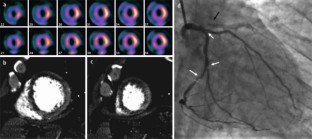

Die Indikation zur kardialen Magnetresonanztomographie (CMR) besteht in erster Linie, wenn eine pharmakologische Belastungsuntersuchung indiziert ist. Mit Dobutamin durchgeführt ist die CMR dann eine Alternative zur Echokardiographie, während die Adenosin-Perfusions-CMR die strahlenfreie Alternative zur Myokardszintigraphie darstellt. Die CMR-Spätaufnahme nach Kontrastmittelgabe stellt den Goldstandard für die Darstellung myokardialer Narben und die Vorhersage einer Erholung der myokardialen Funktion nach Revaskularisierung (Vitalitätsuntersuchung) dar.

The main indication for cardiac magnetic resonance imaging (CMR) is for pharmacologic stress testing. If such a test is indicated, dobutamine stress CMR is an alternative to stress echocardiography and adenosine perfusion CMR is the alternative to nuclear myocardial perfusion imaging but without radiation. Late gadolinium enhancement CMR is the current gold standard for the assessment of myocardial scars and hence is well suited to predict recovery of function in dysfunctional myocardial regions following revascularisation (viability testing).